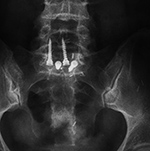

Lumbar spine bony disk strut, pedicle screws, and pedicle rods (AP view) |

20 year-old woman with L1 vertebral body compression fracture treated with T12-L2 posterior spinal fusion using pedicle screws at T12 and L2 with connecting rods on each side. |